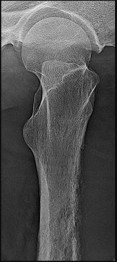

Figures 12a and 12b are a recent radiograph and a whole-body bone scan of an 81-year-old man who has hip pain and difficulty walking. His medical history is significant for obesity, hypertension, chronic kidney disease, and coronary artery disease. An examination demonstrates

moderate tenderness with passive range of motion of the left hip and an inability to actively flex the left hip against gravity. What is the best next step?

This patient has no known history of active malignancy. The radiograph shows a lesser trochanteric avulsion fracture (a fracture routinely associated with an underlying neoplasm). The bone scan reveals no other bone lesions. The femur fracture is statistically most likely to occur because of metastatic disease, but, without other evidence of metastasis, a primary bone sarcoma is possible, and biopsy is recommended before surgical fixation. Observation of this fracture, which is pathognomonic for neoplastic disease, is strongly discouraged.